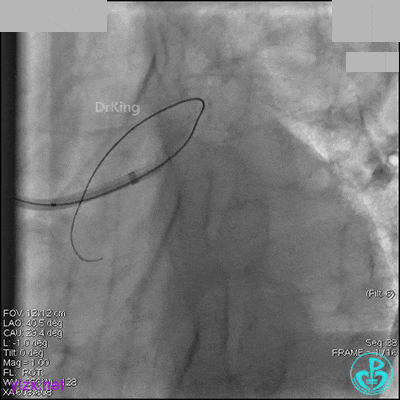

1周后再次上台,右冠脉3级血流,3段局限性严重狭窄,内膜模糊,应该是上次操作夹层遗留下的血肿。

先处理前降支开口严重狭窄并顺利植入前降支到左主干支架。